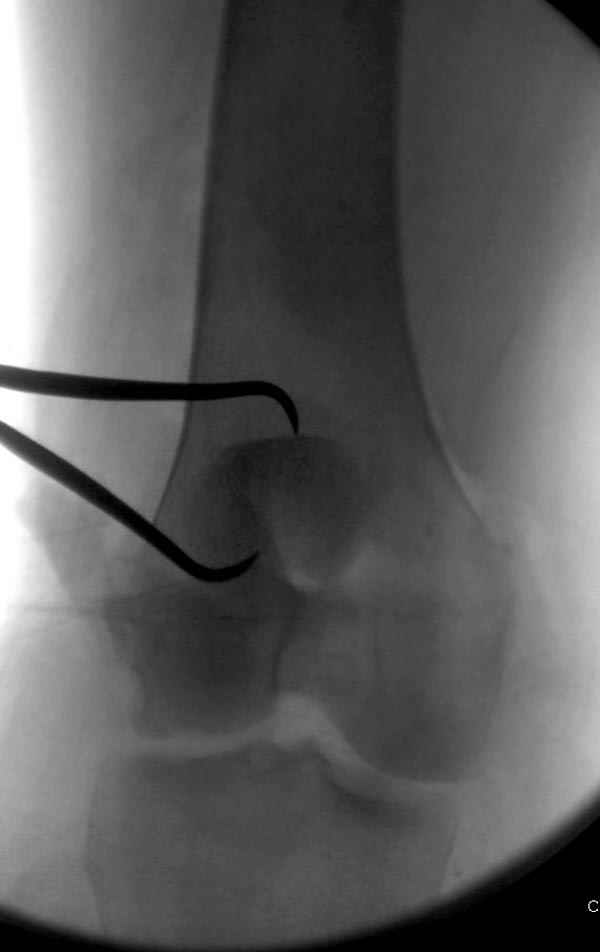

Сегодня досылаю остальные снимки, которые не прошли вчера. Как вчера писал, после фиксации перелома надколенника с дефектом кости и собственной связки, наложили ваккуум и наружный фиксатор. (снимки 4-9)

Внешний фиксатор держим около 6 недель, поэтому был выбран метод фиксации шурупами и еще линия перелома была диагональной, не было нужды в tension band technique, cannulated screws удобнее, провел спицы и по ним шурупы.